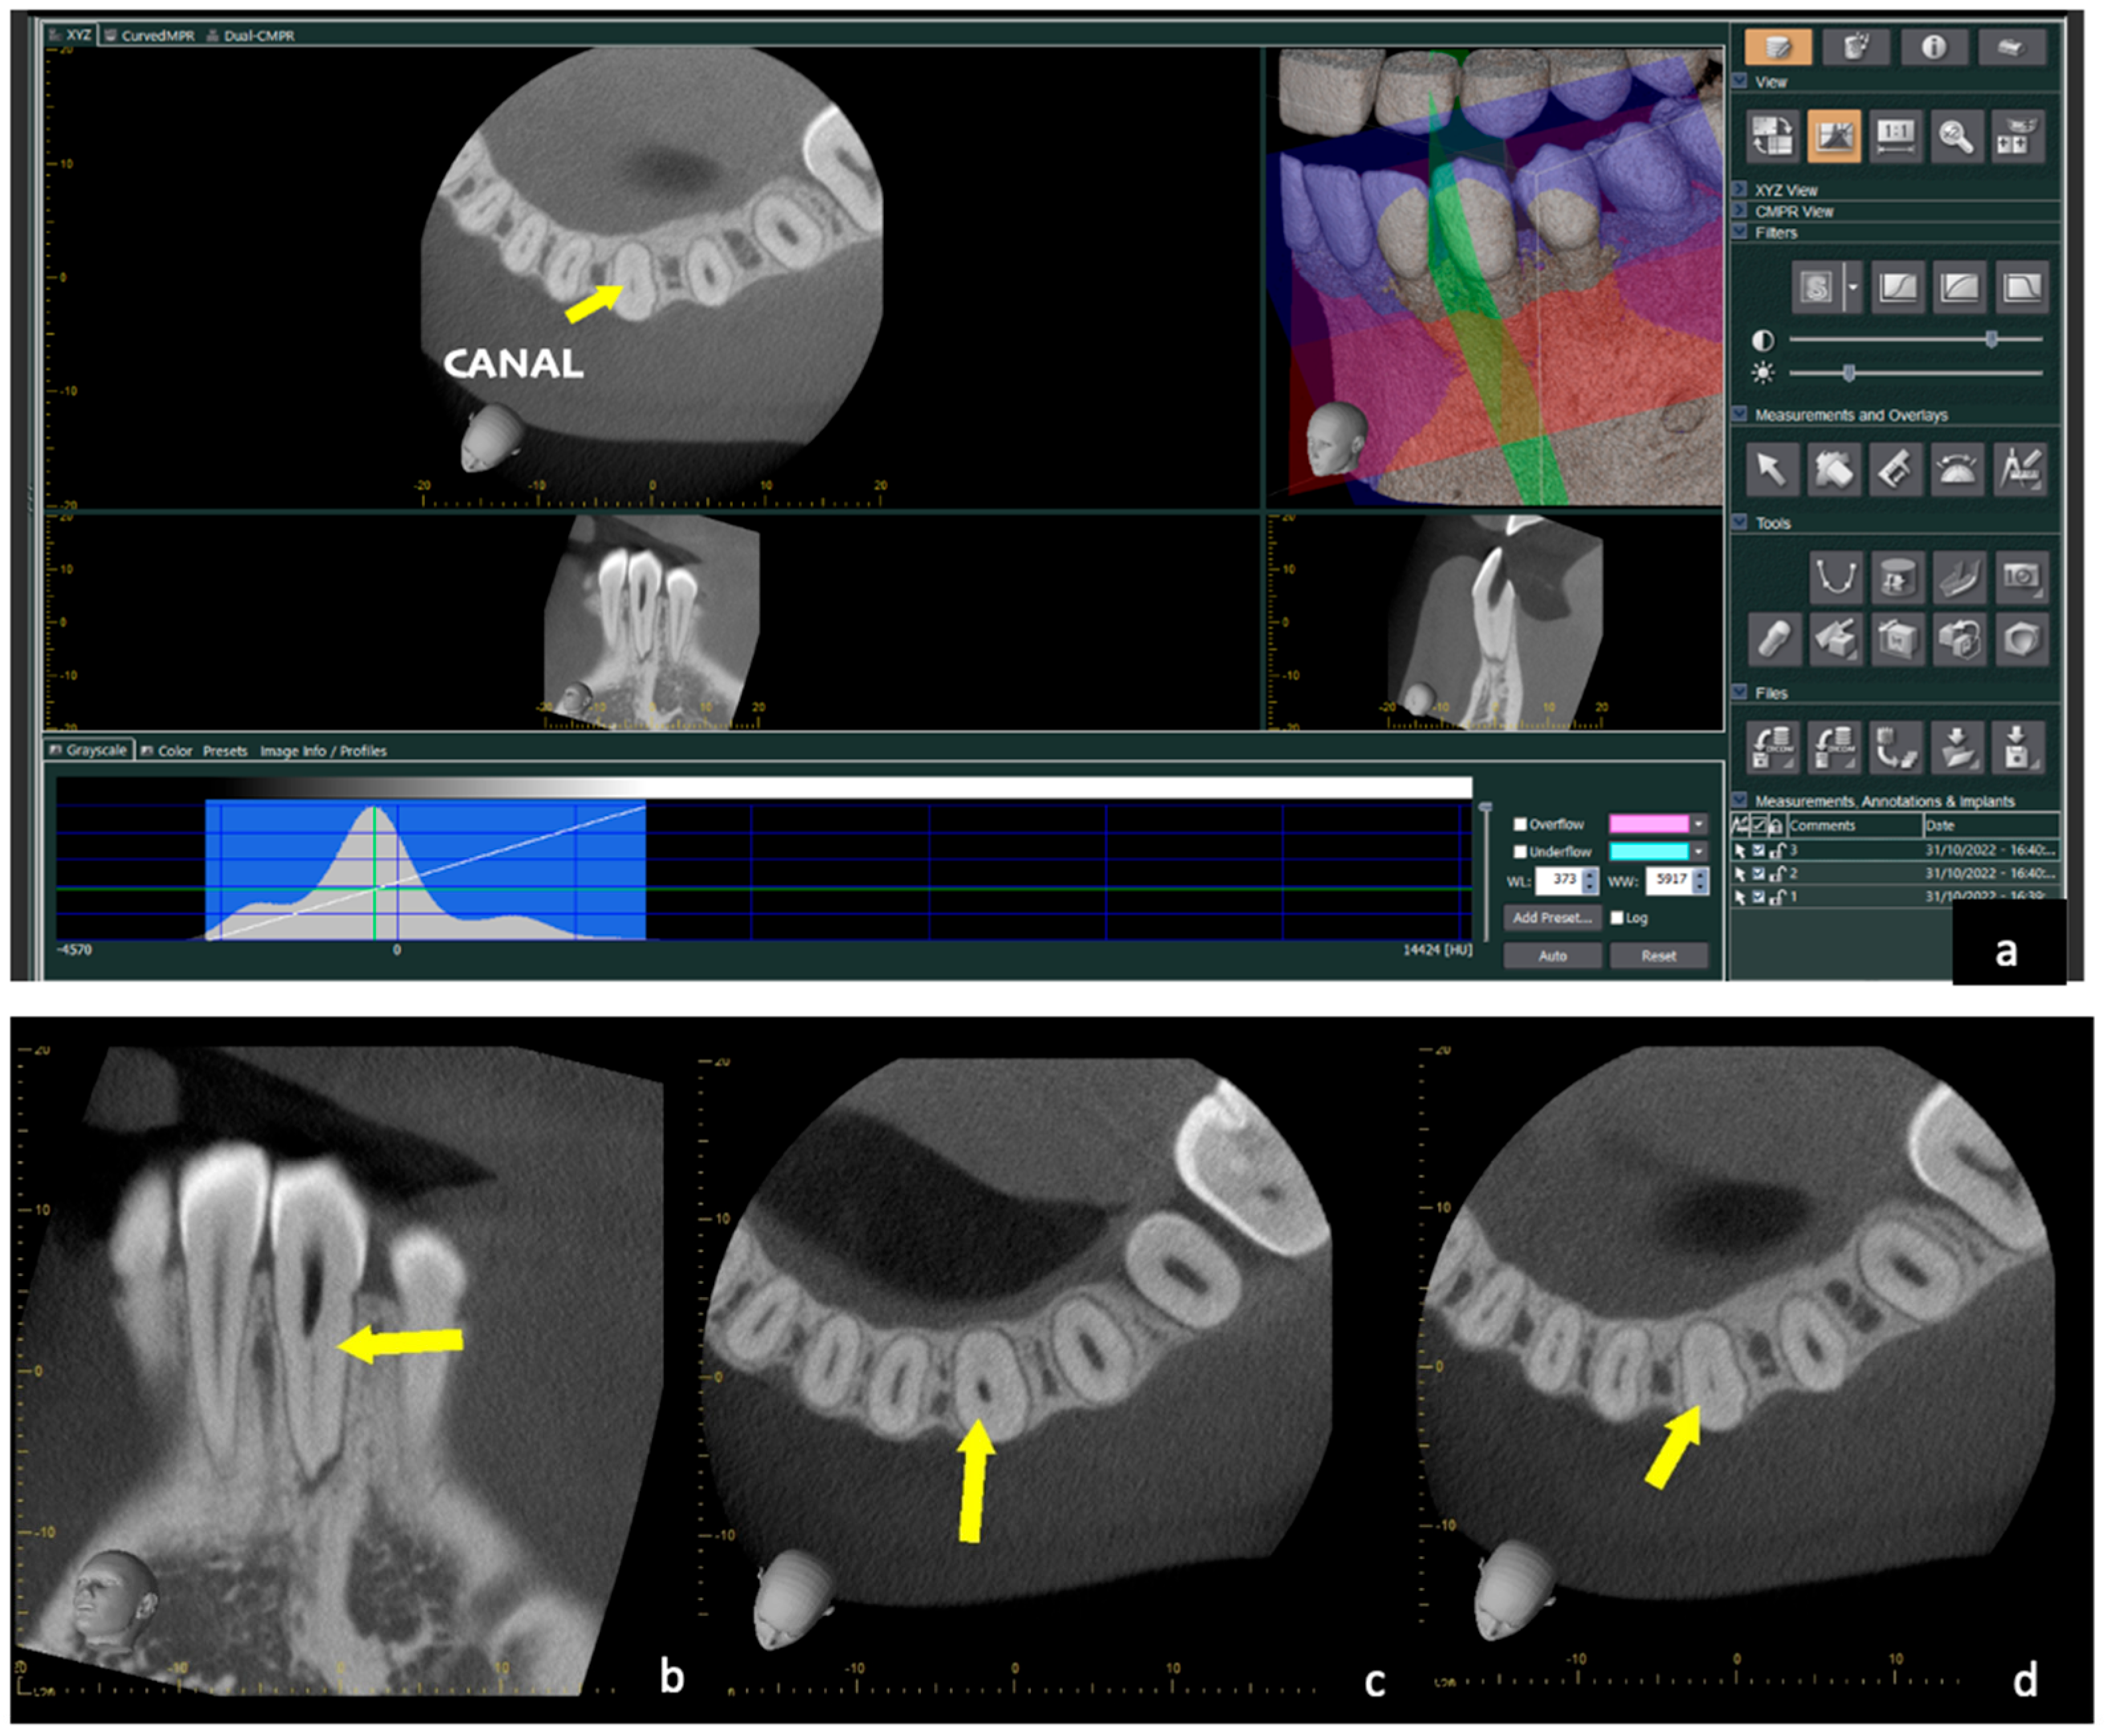

The patient was informed of the anatomical complexity and consented to perform a pre-operative CBCT with a small FOV (Morita Veraview X800, J.Morita, Tokyo, Japan) and high resolution. Before proceeding, written informed consent was given by the patient after reading a patient information sheet. The selected FOV was the lowest available (6 × 7 cm in the lower jaw), using the advanced function (160-micron voxel) and then reconstructing the raw data with 80-micron voxels. The CBCT confirmed a zone of obstruction and a ledge created during the first attempt to negotiate the canal, in the mid/coronal third, and a buccal/lingual curvature (Figure 2 and Figure 3).

Figure 2. (a) Acquisition of 4 × 4 CBCT volume: the yellow arrow in the axial section shows the canal, while the created step is highlighted in the sagittal section. (b) Sagittal section of CBCT: the yellow arrow indicates the canal obstruction and the step created in the first attempt to locate the canal. (c) Axial section of CBCT: the yellow arrow indicates deviation from the canal. Three-dimensional simulation of the drill’s path in relation to the bio-model and the template. (d) Axial section of the most apical CBCT where the yellow arrow indicates the root canal.